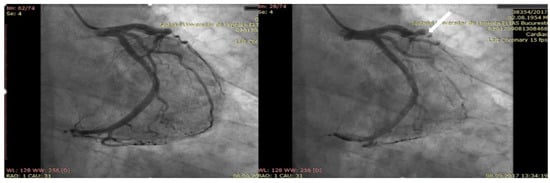

2. Case Presentation